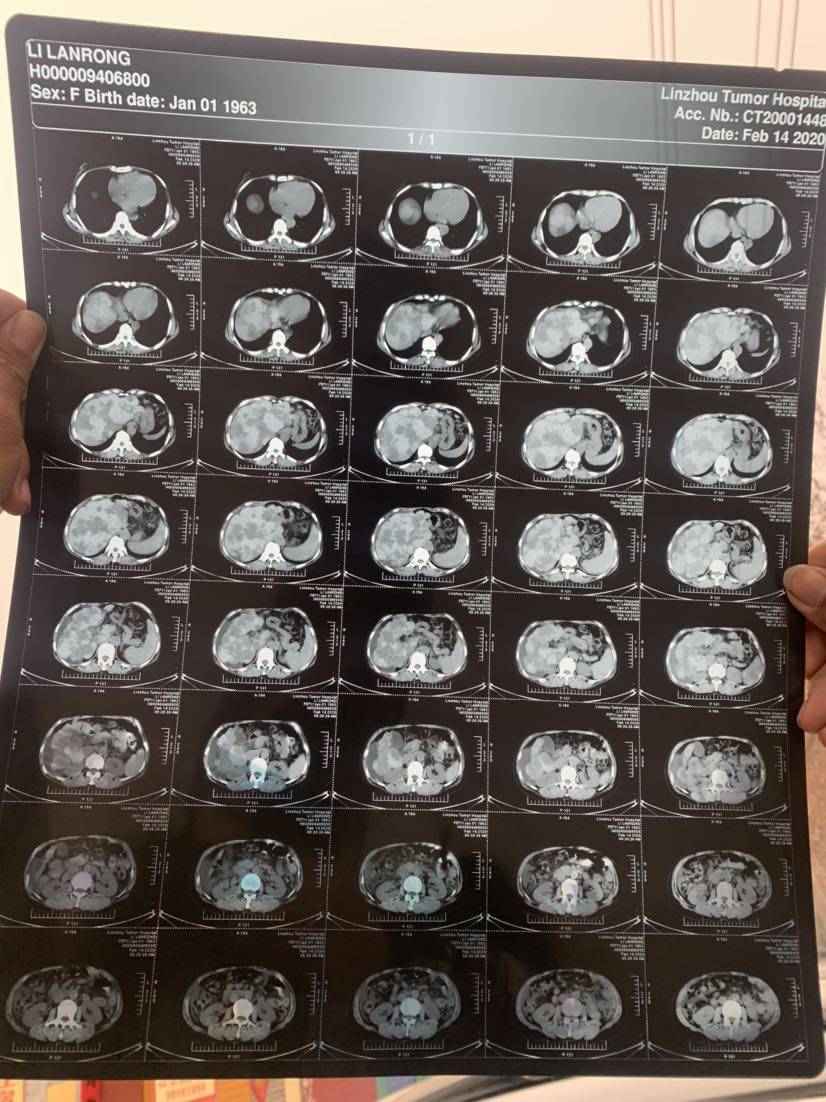

我们肝癌都是吃靶向药,但是不知道你们这种肝转移的是怎么个情况